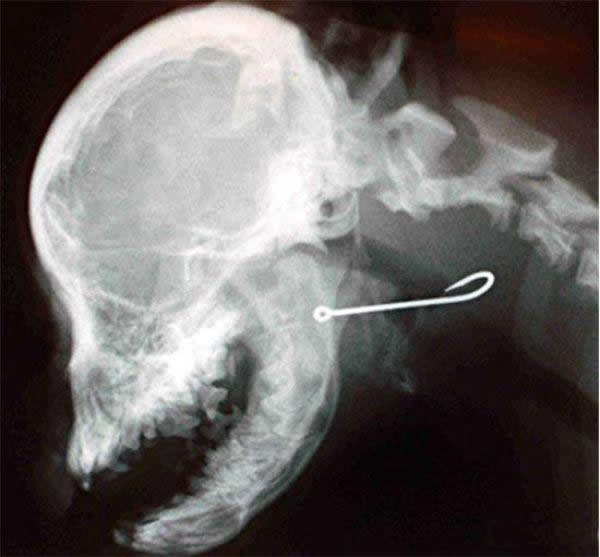

Toys, nails, cell phones, there is an incomplete list of items that are found in the stomachs of four-legged friends